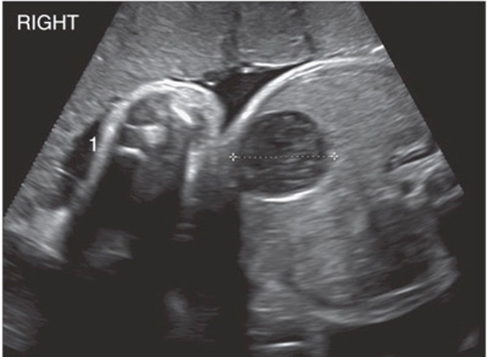

IPKD (ARPKD)

ADPKD

multicystic kidney disease